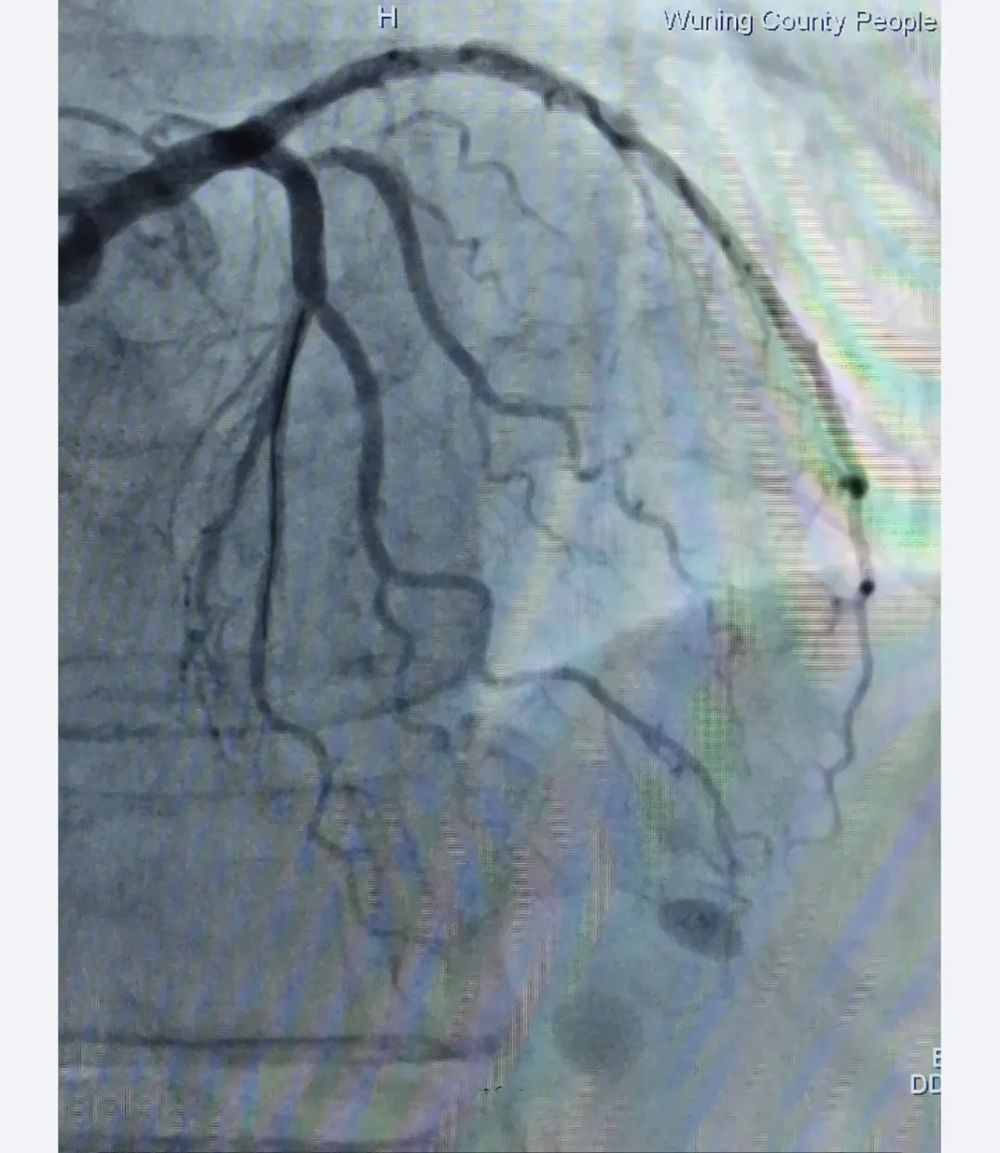

手术前